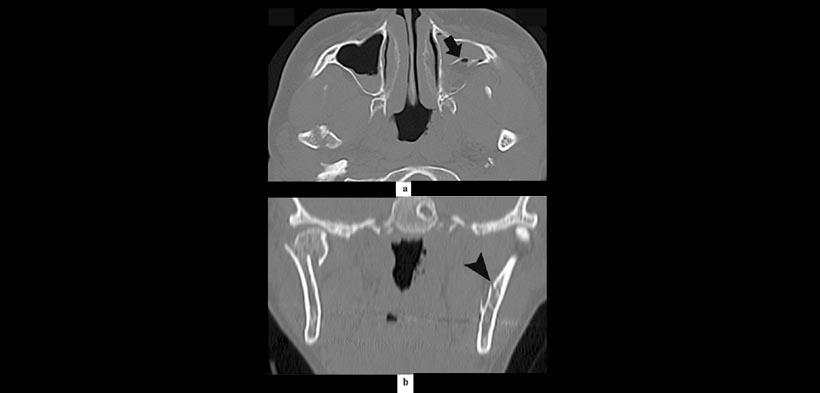

Figura 2. Patrón atípico de una fractura mandibular acompañado de una fractura maxilar posterior en un paciente de 29 años de edad involucrado en un accidente automovilístico. (a) muestra la fractura de la pared posterior del seno maxilar (flecha). (b) fractura sin desplazamiento en la rama mandibular asociados a la fractura anterior (punta de flecha).